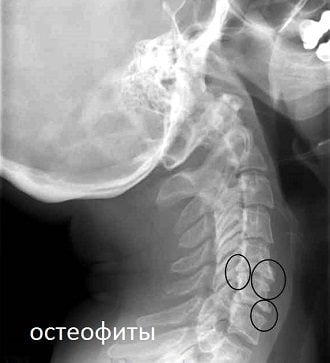

- сформировавшиеся остеофиты (острые костные наросты) сдавливают позвоночную артерию, что приводит к снижению объема крови, поступающей в головной мозг;

- рентгенография шейного отдела в прямой и боковой поверхности для выявления признаков остеохондроза;